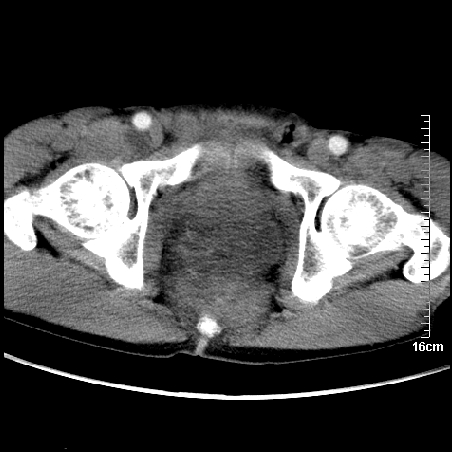

增强:

1、骶尾部巨大软组织肿块,部分骶尾骨以被软组织肿块代替,呈不规则侵蚀;病变突向盆腔内;增强扫描病变呈不均质强化;首先考虑脊索瘤。不支持的一点就是病变内无钙化。

2、发生于骶尾椎者须与骨巨细胞瘤鉴别,骨巨细胞瘤一般发在上疗骶椎,肿瘤内无钙化,一般无侵袭性生长的表现。